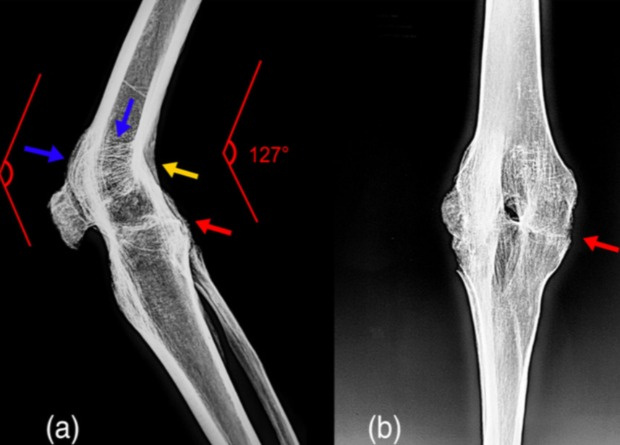

Анкилоз коленного сустава известен и в археологическом контексте. По всей видимости, самым известным примером служат останки отца Александра Македонского — царя Филиппа II, который за три года до его убийства в 336 году до нашей эры получил ранение копьем в ногу, оставившее его хромым из-за развития анкилоза. Похожую патологию ученые обнаружили на останках женщины 36–45 лет, погребенной в английском средневековом некрополе около 1250–1400 годов. Известны такие останки и в Китае, где в ходе раскопок в Синьцзяне археологи нашли останки мужчины 50–65